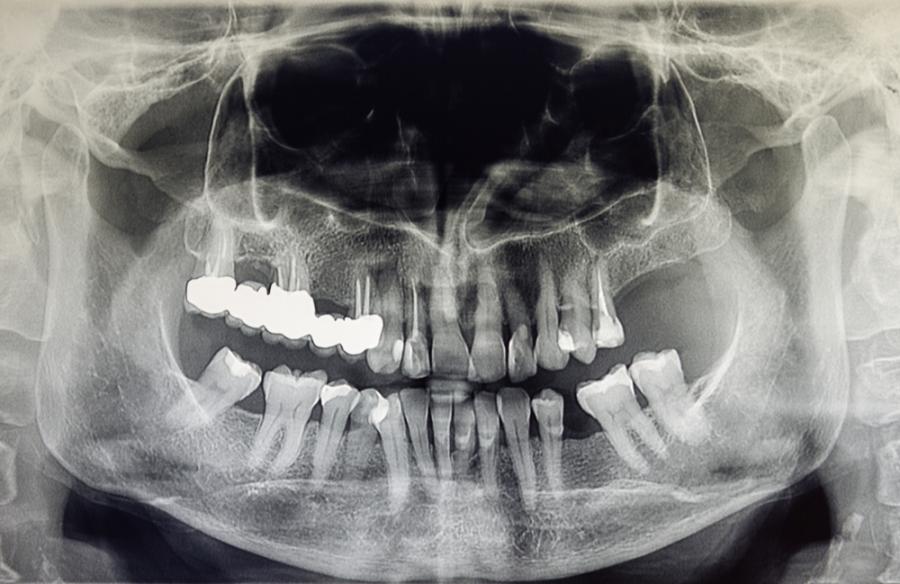

След няколко години на постоянен прием на Radithor Байърс започнал да отслабва, получавал постоянни главоболия и много от зъбите му изпопадали. Костите му започвали малко по малко да се разпадат.

Според него „цялата горна челюст, с изключение на два предни зъба, както и по-голямата част от долната челюст, били премахнати“. Адвокатът заявил, че „цялата костна тъкан в тялото, която била останала, се разпадала, а в черепа му се появявали дори дупки“.

Байърс научава, че състоянието му е смъртоносно, едва няколко седмици преди да почине на 51-годишна възраст. По това време той разполагал само с шест зъба. Погребали го в оловен ковчег.